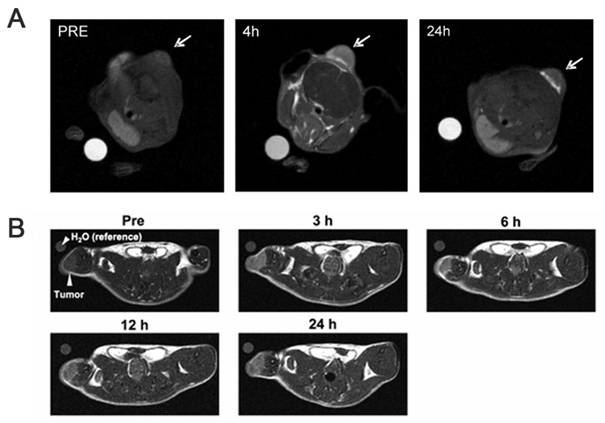

4. Visual evaluation of boron neutron-capture therapy